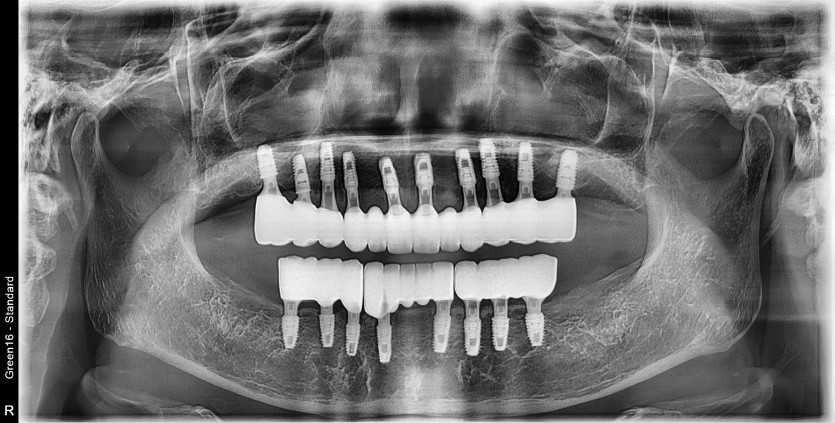

만 61세 전체 임플란트 증례

전체 임플란트 증례입니다.

18개의 임플란트로 완성하였습니다.